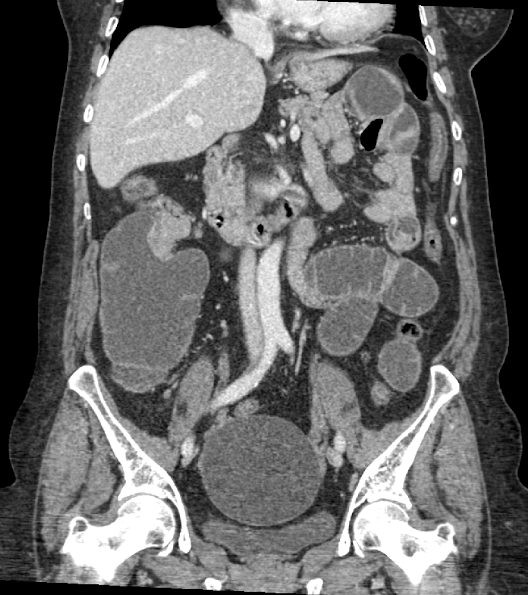

TC abdominal

HALLAZGOS RADIOLÓGICOS